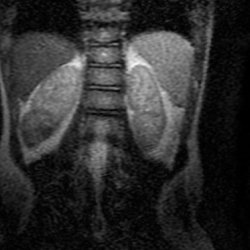

МРТ без контраста , несколько снимков прикрепляю.